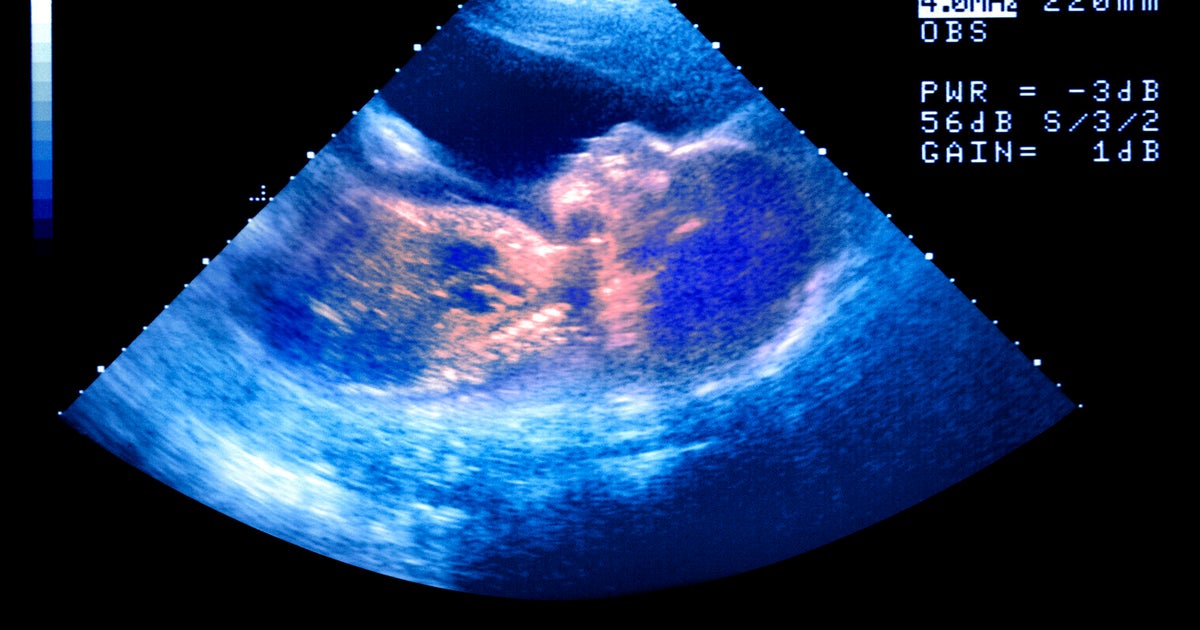

How Common Is Bad News At 20 Week Scan All You Need To Know Ada Jennifer. Now, let's step back for a moment and delve into what birth defects entail more generally. The 20-week scan, also known as the mid-pregnancy or anomaly scan, is a crucial ultrasound examination usually performed between 18 and 22 weeks of pregnancy